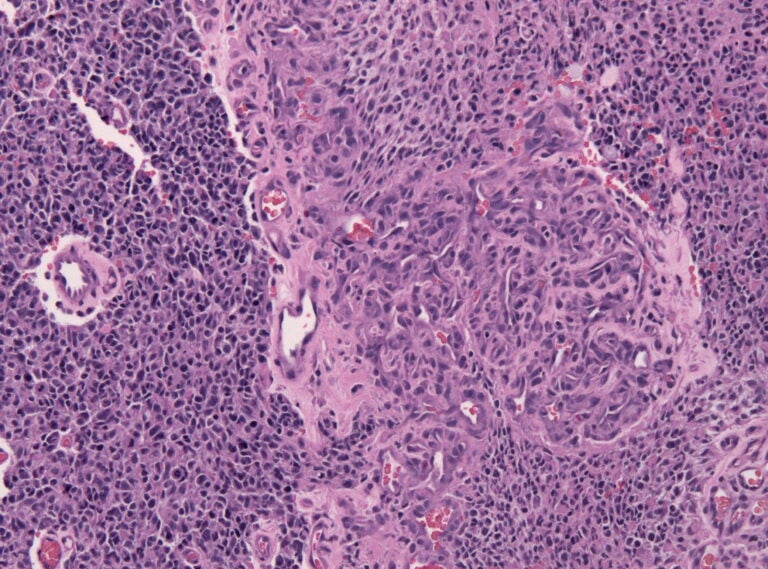

Biopsy specimen of a glioblastoma with prominent micovascular proliferation (formation of a mulitlayered "glomeruloid tuft", HE stain). (Jensflorian, CC BY-SA 3.0 <https://creativecommons.org/licenses/by-sa/3.0>, via Wikimedia Commons)